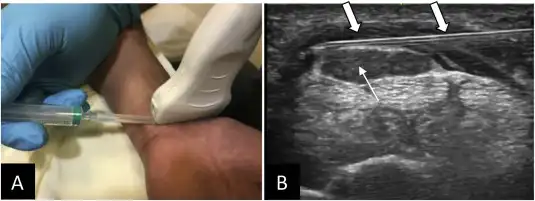

- 2010s–present: Controlled trials emerge, especially for entrapment neuropathies (e.g., carpal tunnel, ulnar neuropathy), and technique papers on ultrasound-guided perineural hydrodissection with D5W.

The suggested mechanism for Peripheral Nerve Injection Therapy (PIT) involves injecting D5W around painful cutaneous or peripheral nerves. This approach may help reduce TRPV1-mediated hypersensitization, dilute inflammatory mediators, and provide mechanical separation of the nerve (hydrodissection), which could result in reduced pain and enhanced function. Mechanistic reviews, including those from PM&R Now, provide a comprehensive overview of the preclinical rationale.

Ultrasound-guided greater occipital nerve hydrodissection with 5% dextrose showed promising symptom relief; provides practical positioning and approach details.